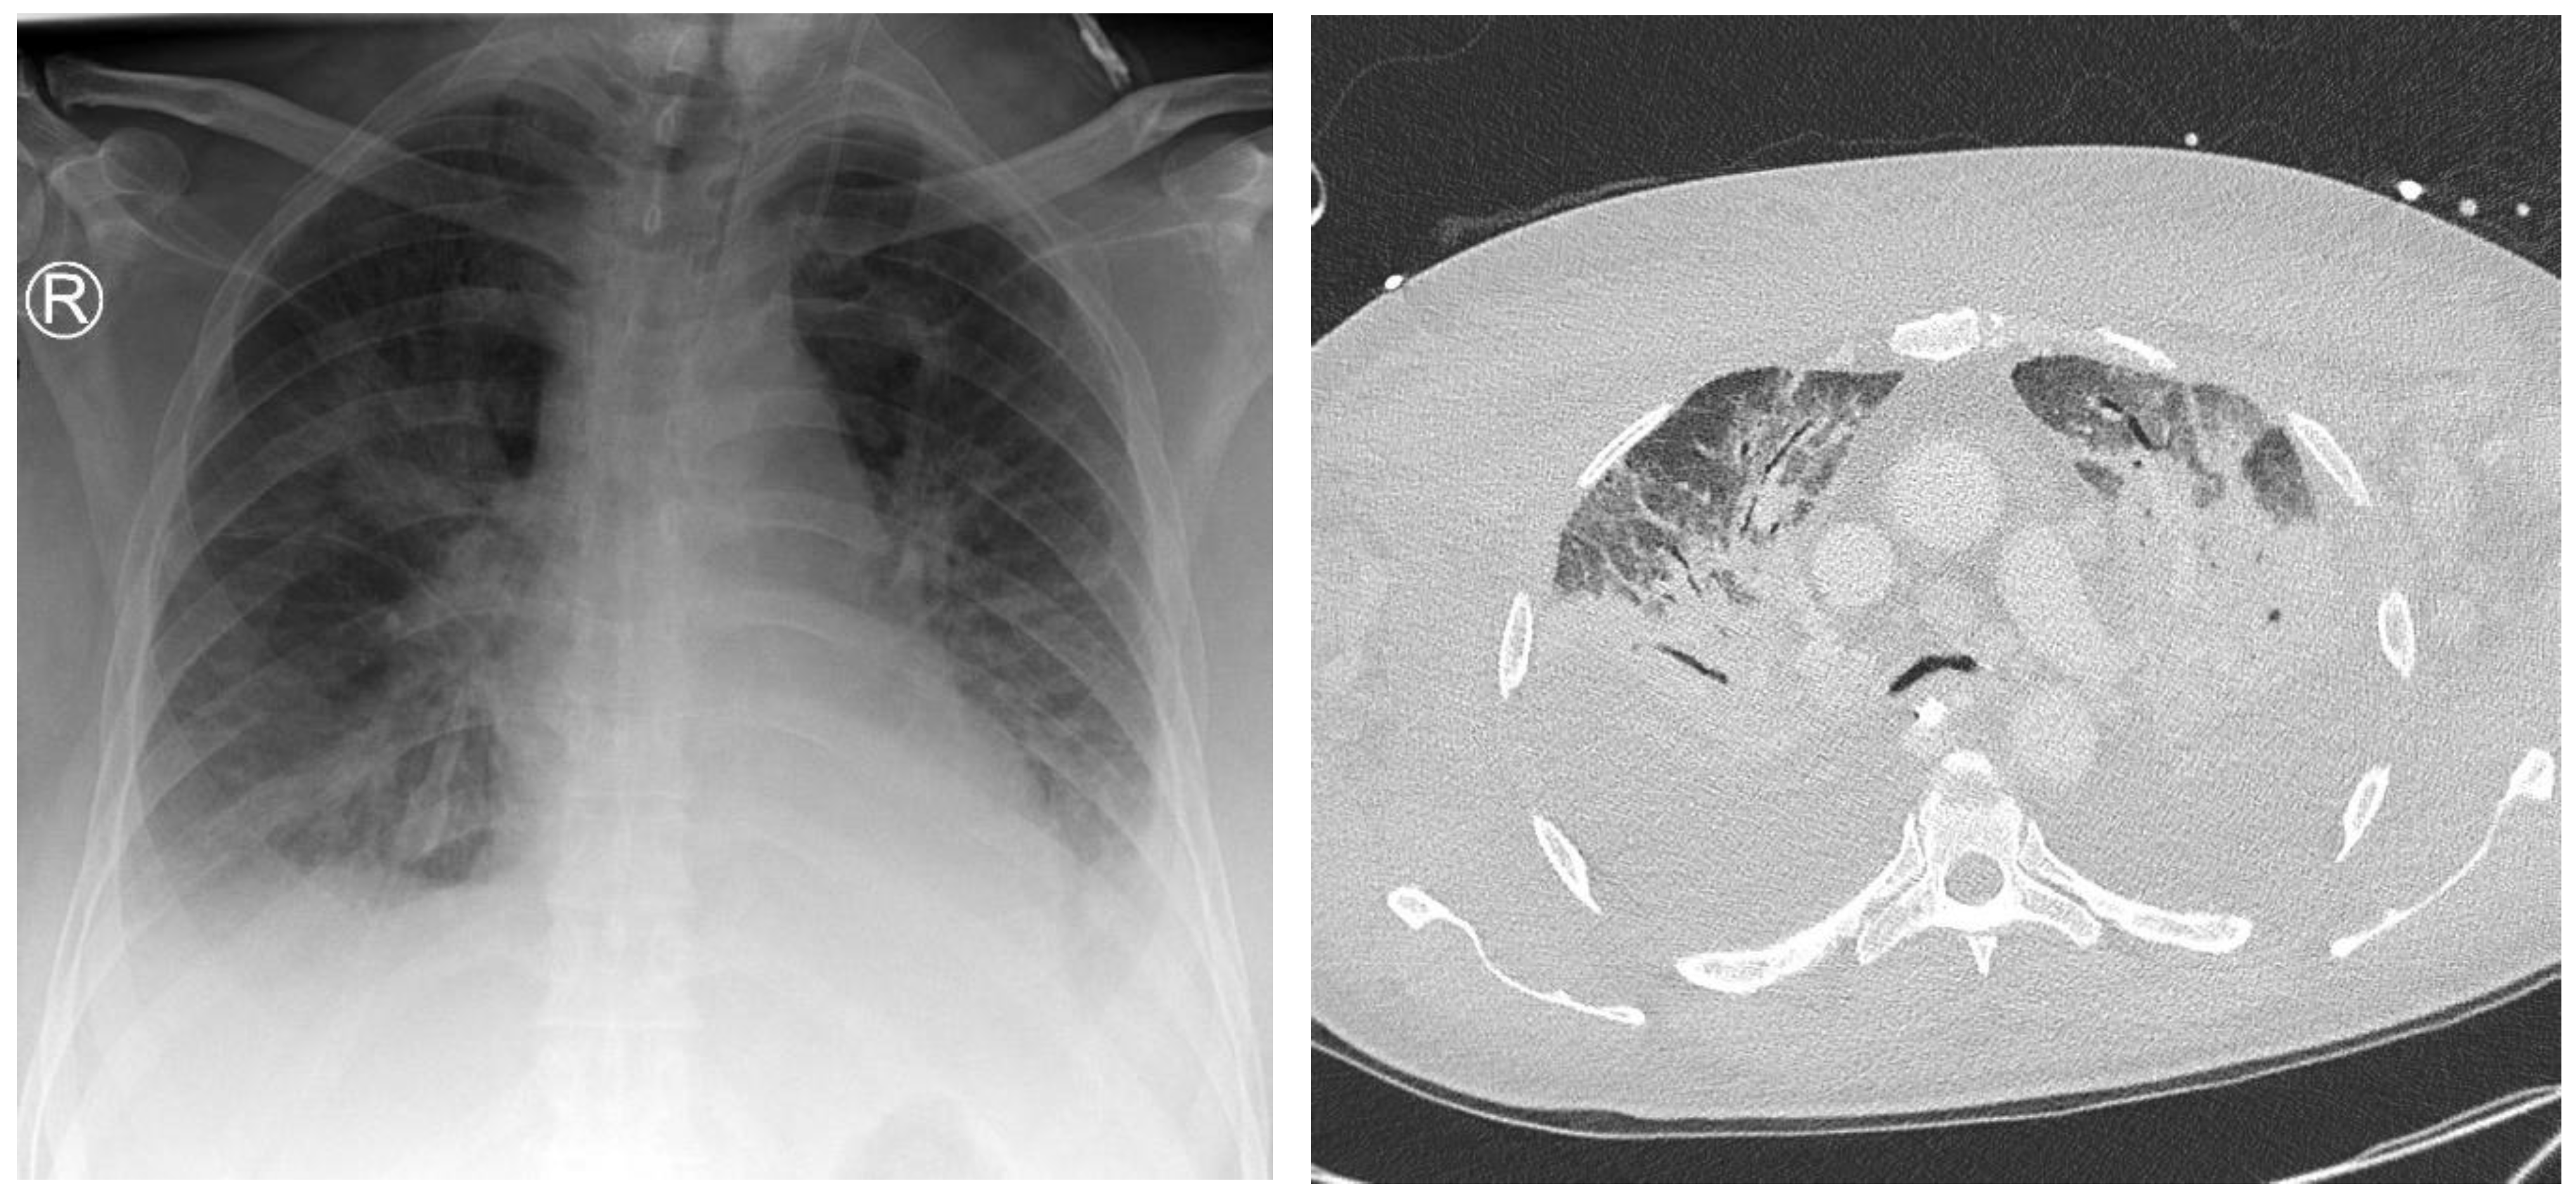

The distribution of thoracic foci was concentrated primarily in three areas: the lungs, mediastinum, and sternum. Of the thoracic findings, 90 foci were present in the lungs, representing 97.8% of the total, while the mediastinum and sternum each contained one focus (refer to Table 3). Pulmonary foci demonstrated high diagnostic conclusiveness, with 75.6% definitively diagnosed. This highlights the effectiveness of CT imaging in accurately detecting and characterizing lung-associated inflammatory processes, as exemplified in Figure 3.

Figure 3. A 26-year-old intensive care patient with elevated inflammatory markers. Typical morphologic signs of pneumonia in the right lower lobe are evident, including ground-glass opacity (GGO), bronchial wall thickening, and pleural effusion.